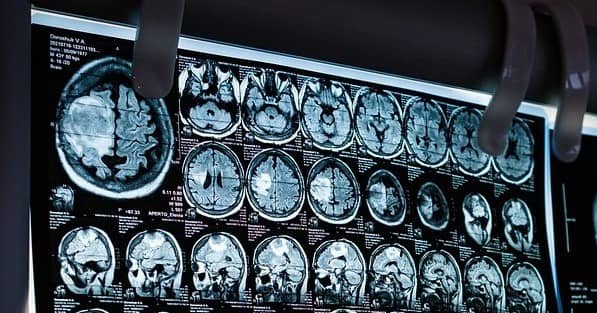

신경가소성(Neuroplasticity)이란 뇌가 환경과 경험에 따라 변화하고 적응하는 능력을 의미합니다. 과거에는 인간의 뇌 구조가 고정되어 있다고 여겨졌으나, 현대 뇌과학 연구를 통해 뇌는 평생 동안 새로운 신경 연결을 형성하고 재조정할 수 있음이 밝혀졌습니다. 이는 정신 건강에도 중요한 영향을 미치며, 특히 우울증, 불안 장애, 외상 후 스트레스 장애(PTSD) 등의 정신 질환에서 신경가소성의 역할이 크게 작용합니다. 예를 들어, 하버드 의과대학(Harvard Medical School) 연구에서는 명상과 같은 심리적 훈련이 신경가소성을 촉진하여 스트레스 완화에 도움을 준다는 결과를 발표했습니다. 또한, 옥스퍼드 대학교(Oxford University)에서 진행한 연구에서는 긍정적인 사고 습관을 가진 사람들이 전두엽(prefrontal cortex)의 활동이 증가하며, 이는 자기 조절 능력을 강화하여 정신 건강을 유지하는 데 도움이 된다는 점을 강조했습니다.

스트레스는 신경학적으로 해마(hippocampus), 편도체(amygdala), 시상하부-뇌하수체-부신축(HPA axis) 등의 뇌 영역과 밀접한 관련이 있습니다. 특히 편도체는 스트레스 자극을 감지하고, HPA 축을 활성화하여 코르티솔(Cortisol)과 같은 스트레스 호르몬을 분비합니다. 코르티솔 수치가 일정 수준을 넘어서면 해마의 기능이 저하되고, 이는 기억력 감소 및 감정 조절 문제를 초래할 수 있습니다. MIT(Massachusetts Institute of Technology)에서 수행된 연구에서는 만성 스트레스가 해마의 신경세포 생성을 억제하며, 이로 인해 불안과 우울증 발병 위험이 증가한다는 점이 밝혀졌습니다. 또한, 일본 도쿄대학교(Tokyo University) 연구에서는 지속적인 스트레스가 뇌의 백질(White Matter) 감소를 유발하여 장기적인 정신 건강 악화와 관련이 있다는 점을 강조했습니다.